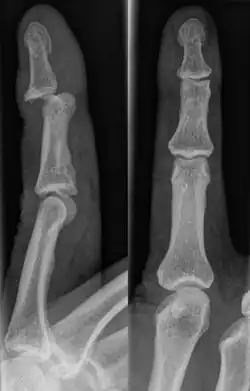

A jammed finger can generally be diagnosed by a physical examination. Bone or joint deformity may indicate potential dislocations or fractures.[6] The basic structure of the finger includes three bones with joints in between each.[9] The joint closest to the tip is the distal interphalangeal (DIP) joint. The next joint, moving closer to the hand, is the proximal interphalangeal (PIP) joint. The thumb differs by only having two bones and one interphalangeal joint.[10]

The injured finger may be examined to determine where the pain is worst.[3] If the finger is sprained or dislocated, pain will be worse at the joint rather than the bone.[3] Due to the risk of dislocations or fractures, X-rays should be conducted prior to testing joint stability. This allows for prior detection of a dislocation or fracture.[3] It is recommended that a variety of views (lateral, oblique, and anteroposterior) are observed.[3] In extremely painful cases, a digital nerve block may be done to better assess the finger. This is where anesthetic is injected to either side of the base of the affected finger to reduce pain.[3]

Injuries that force the finger towards the back of the hand may cause damage to the volar plate.[12] This is a ligament on the palm side of the hand that prevents hyperextension.[13] Volar plate damage may be assessed by pressing the finger bones from the back towards the palm. If either individual bone of the affected joint moves freely towards the palm, it is indicative of a tear.[2] Tears of the volar plate may lead to an avulsion fracture – when a piece of bone is pulled off with the ligament.[13] This is due to the thickness and strength of the ligament.[14] To rule out an avulsion fracture, x-rays are frequently utilized in evaluation of suspected volar plate tears.[12] Volar plate avulsions are most evident on lateral views.[2]

Fractures

Fractures are instances where the bone's structural integrity has been compromised.[20] If a jammed finger produces a fracture, pain will be greatest at the bone as opposed to the joint.[2] There may also be visual deformation of the bone itself.[6] As with any skeletal injury, an x-ray can be conducted to verify the presence of a fracture.[1] The distal phalanx is especially vulnerable to avulsion fractures.[1] These avulsion fractures are common following a first time dislocation of the DIP.[1]